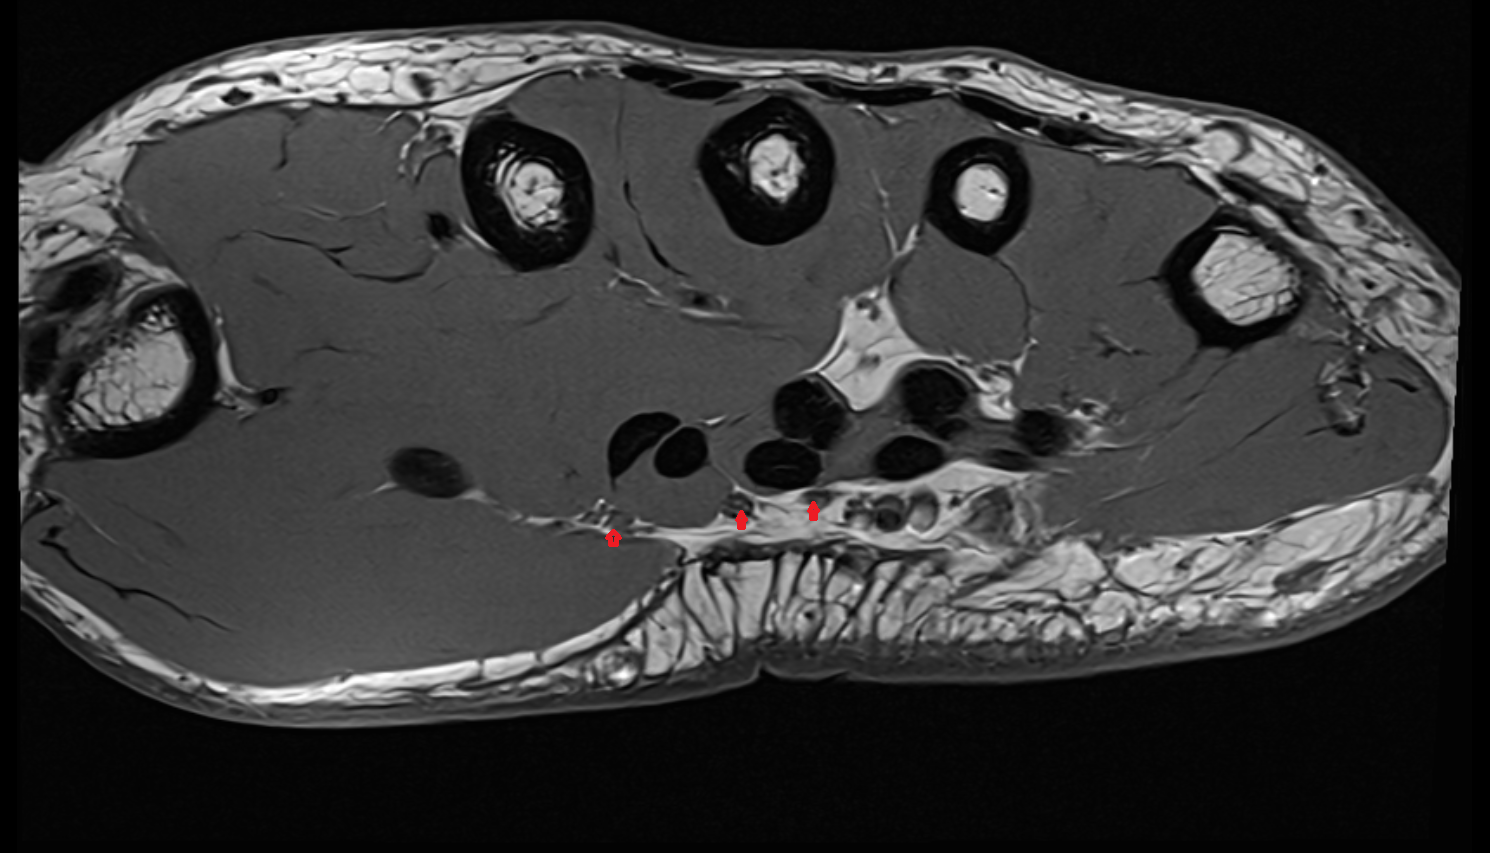

- Plantar aponeurosis

- Achilles tendon

- Calcaneus

- Talus

- Tibialis posterior tendon

- Flexor digitorum longus tendon

- Flexor hallucis longus tendon